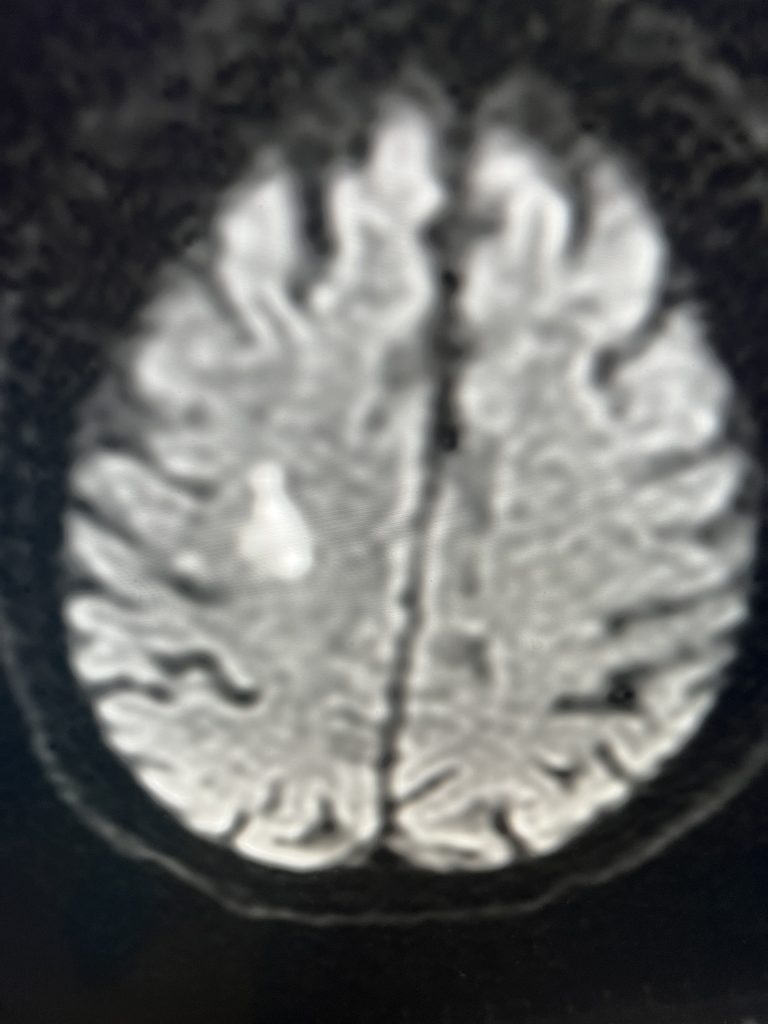

Fig. 2 – Pre-operative imaging shows multiple areas of most likely embolic stroke in the right corona radiata.

MRI imaging using the diffusion-weighted image sequence, which is highly sensitive for acute stroke showed multiple areas of most likely embolic stroke in the right frontal white matter (Figure 1) as well as the right corona radiata (Figure 2).